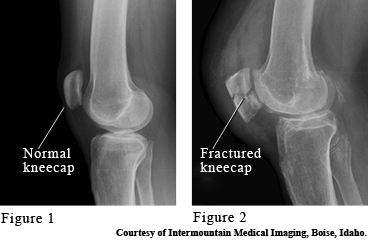

The kneecap (patella) is a bone that protects the front of the knee joint. It takes the brunt of any blows to the knee, such as a fall onto the knee or hitting the knee against the dashboard. Symptoms of a broken kneecap (fracture) are swelling and pain, especially when moving the knee back and forth.